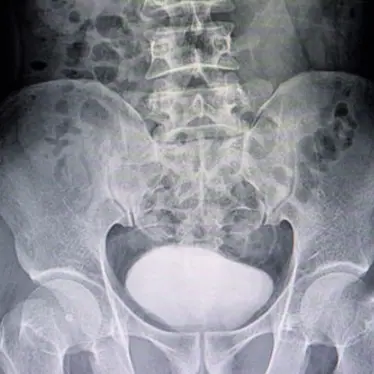

EOS imaging is a low-dose 3D X-ray system that reduces radiation exposure by 50-80%, ensuring the safest imaging for your child. It helps doctors diagnose and plan treatments for spine, hip and knee conditions. Children’s is the only hospital in Nebraska offering EOS imaging.

Children’s Nebraska offers a low dose, 3D X-ray imaging system — the EOS System® — that uses 50 to 80% less radiation than a typical X-ray. This enables us to provide As Low As Reasonably Achievable (ALARA) imaging, which means it limits your child’s exposure to radiation to the lowest and safest amount possible to still get the results we need.

With EOS, our physicians can make an informed diagnosis and develop treatment plans for your child’s spine, hip or knee condition. Children’s is the only hospital in Nebraska offering EOS imaging.

The EOS System is primarily used to assess patients with spine, hip and leg disorders. Because of the low radiation dose, EOS is ideal for progressive conditions that require frequent medical imaging, such as scoliosis.

An EOS exam uses two very fine X-ray beams that can capture both front and side images at the same time. Your child will stand or be seated while the EOS System scans their body.

The EOS System can image the entire body in less than 20 seconds and can reduce the total procedure time to about four minutes.